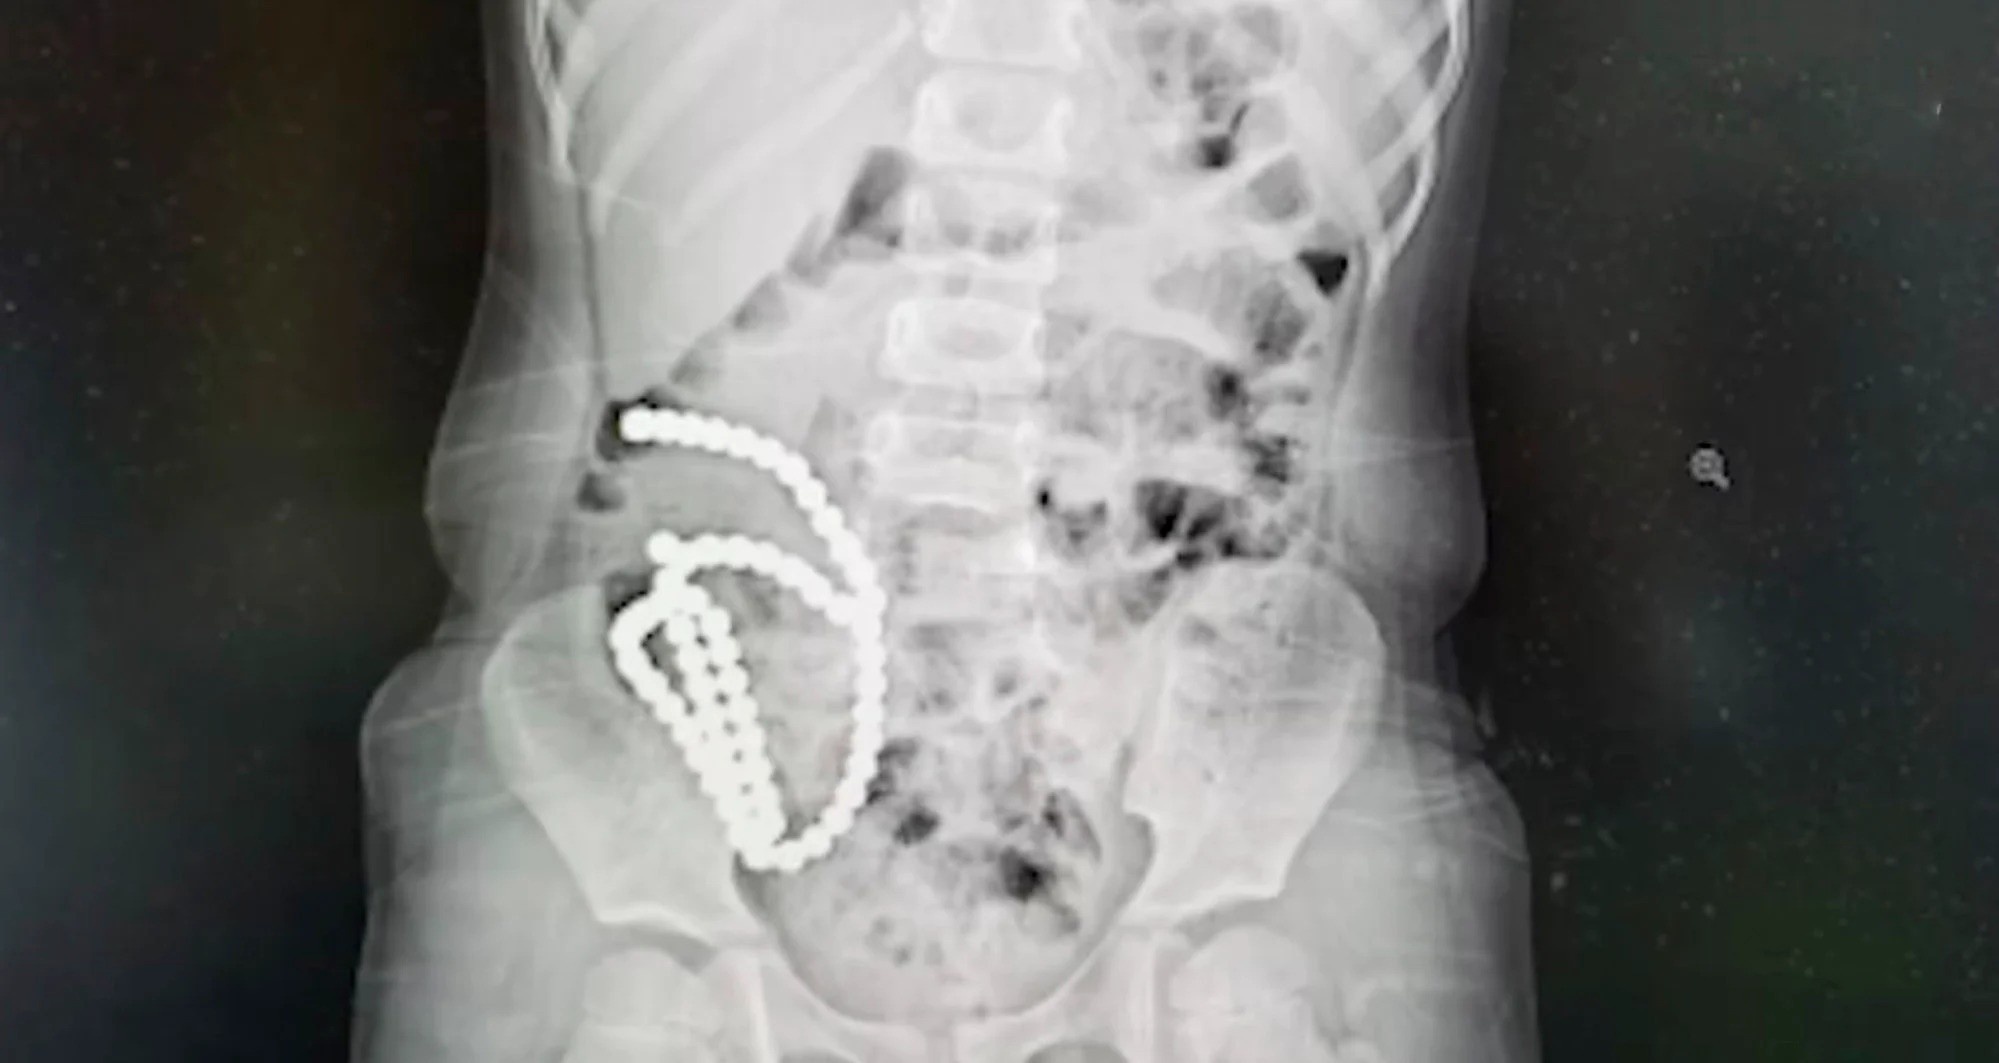

Đau bụng suốt một tháng, bé gái 4 tuổi được đưa đến bệnh viện để làm phẫu thuật. Các bác sĩ lấy ra 61 hạt nam châm trong bụng bé gái và phải vá nhiều lỗ thủng trong ruột.